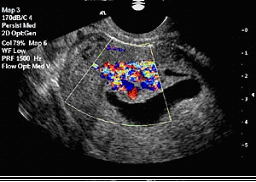

![]() Цветно доплерово изображение на маточни полипи, наблюдвана при сонохистерография. |

Сонохистерографията (хидротубация) е нова технология, показваща по-добре изображението на маточната кухина. При нея под ултразвуков контрол в маточната кухина се вкарва стерилен физиологичен разтвор с гъвкав и пластичен катетер, поставен в шийката на матката. Физиологичният разтвор разширява маточната кухина и осигурява отличен контраст с маточната лигавица, като с това подобрява визуализацията на маточната и ендометриална патология. Тази технология може също така да се използва за оценка на маточните тръби чрез изливане на флуид към таза. Цветното доплерово изображение показва движението на ултразвуковите вълни през контрастната среда вътре в тръбите. С хидротубацията се проверява и проходимостта на маточните тръби – това е безболезнена процедура под ултразвуков контрол, след която често пъти може спонтанно да настъпи бременност поради реканализация на малки сраствания